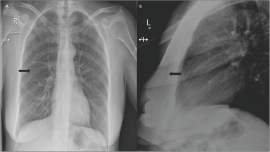

Figure 3: Post localisation lateral mammogram of the right breast show a hook-wire retracted into the breast and lodged into the pectoral muscle.

A similar incident occurred at our institution whereby a wire completely retracted into the pectoral muscle of a patient with a deeply situated lesion against the chest wall; no wire was visible outside the skin (Figures 3 & 4), complicating the surgical excision. Furthermore, the site of skin entry for the wire is not always consistent with the site of skin entry for the surgeon's incision, which may limit the surgeon's approach11. Finally, wire placement is done on the day of surgery, which may potentially cause conflicts between theatre and radiology schedules11. Consequently, alternative techniques have been developed, validated and proven to be superior to HWL. Techniques such as radioactive seed localisation (RSL) using 125I titanium seeds provide precise localisation, reduced procedure and operation time, improved rate of clear margins with reduced excision of healthy breast tissue, and higher acceptability by patients, surgeons, radiologists, and pathologists2-5, 11. Moreover, RSL performed more than one day in advance to surgery offers flexibility in scheduling localisation procedures and surgery, in addition to technical ease of post localisation mammograms without interference of wires. It can be performed at the same time as sentinel lymph node biopsy.

Figure 4: Frontal (A) and lateral (B) chest x-ray show a hook-wire (arrows) retracted into the right breast.